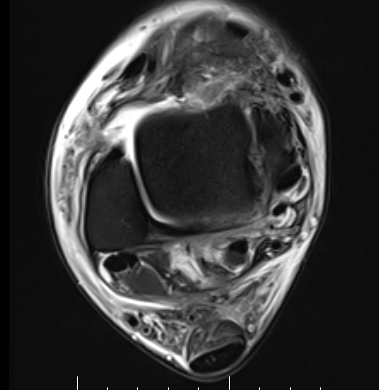

MRI

ATFL normal

Torn ATFL